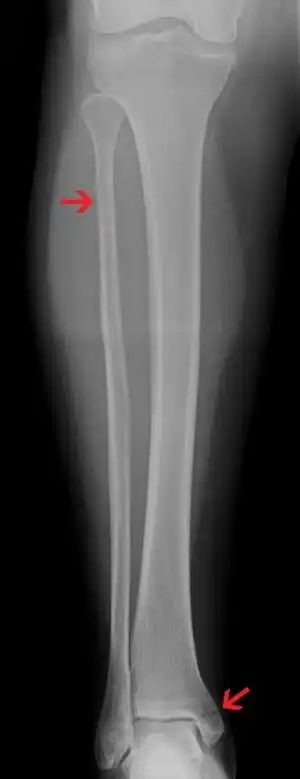

| A Maisonneuve fracture with arrows marking the location of the two fractures | |

A Maisonneuve fracture is an injury at the ankle with an associated break of the lower leg near the knee.[5] The ankle injury involves a tear of the ligament connecting the two bones of the lower leg, the tibiofibular syndesmosis.[5] There may also be a break of the medial malleolus or rupture of the deltoid ligament of the ankle.[3] Symptoms typically include tenderness over the medial ankle and outside aspect of the upper part of the lower leg.[1]

It typically results from excessive external rotation of the ankle.[3] X-rays typically show widening of the ankle joint, though this may be subtle.[3][1] Stress views may be useful in unclear cases.[4] People may not mention pain around the knee due to the greater degree of pain in the ankle.[6] It is classified as a type C3 ankle fracture according to the Danis-Weber classification system.[7]

Ankle Xrays are used to detect widening of the tibiofibular syndesmosis or medial clear space. The medial clear space is the area between the talus of the ankle and the medial malleolus. Damage to the deltoid ligament and syndesmotic ligaments result in mortise instability, causing the talus to laterally shift and widen the medial clear space.[9][16] A study found that the medial clear space size of a normal ankle and an injured ankle measured at 4 millimetres and 5.4 millimetres in length respectively.[14] To confirm diagnosis, full-leg radiographs are used to inspect for fractures of the proximal fibula and widening of the interosseous clear space (or tibiofibular clear space). The interosseous clear space is the area between the medial side of the fibula and lateral side of the tibia. A peer-reviewed study, published in Injury in 2004, found that an interosseous clear space greater than 10 millimetres indicates diastasis of the syndesmotic ligaments.[9]